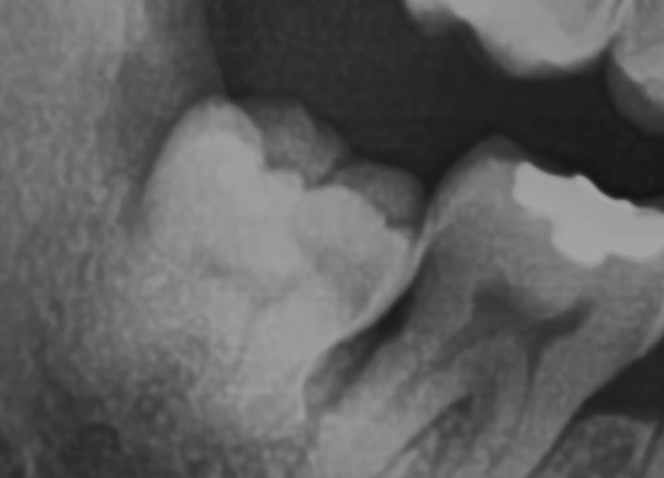

2) 복잡매복: 아래 사진을 보면 사랑니가 누워있어, 그냥 뽑을 수 없는 것을 복잡매복이라 하고, 마취를 하고, 사랑니 일부를 절단한 후에 뽑는다고 하네요.